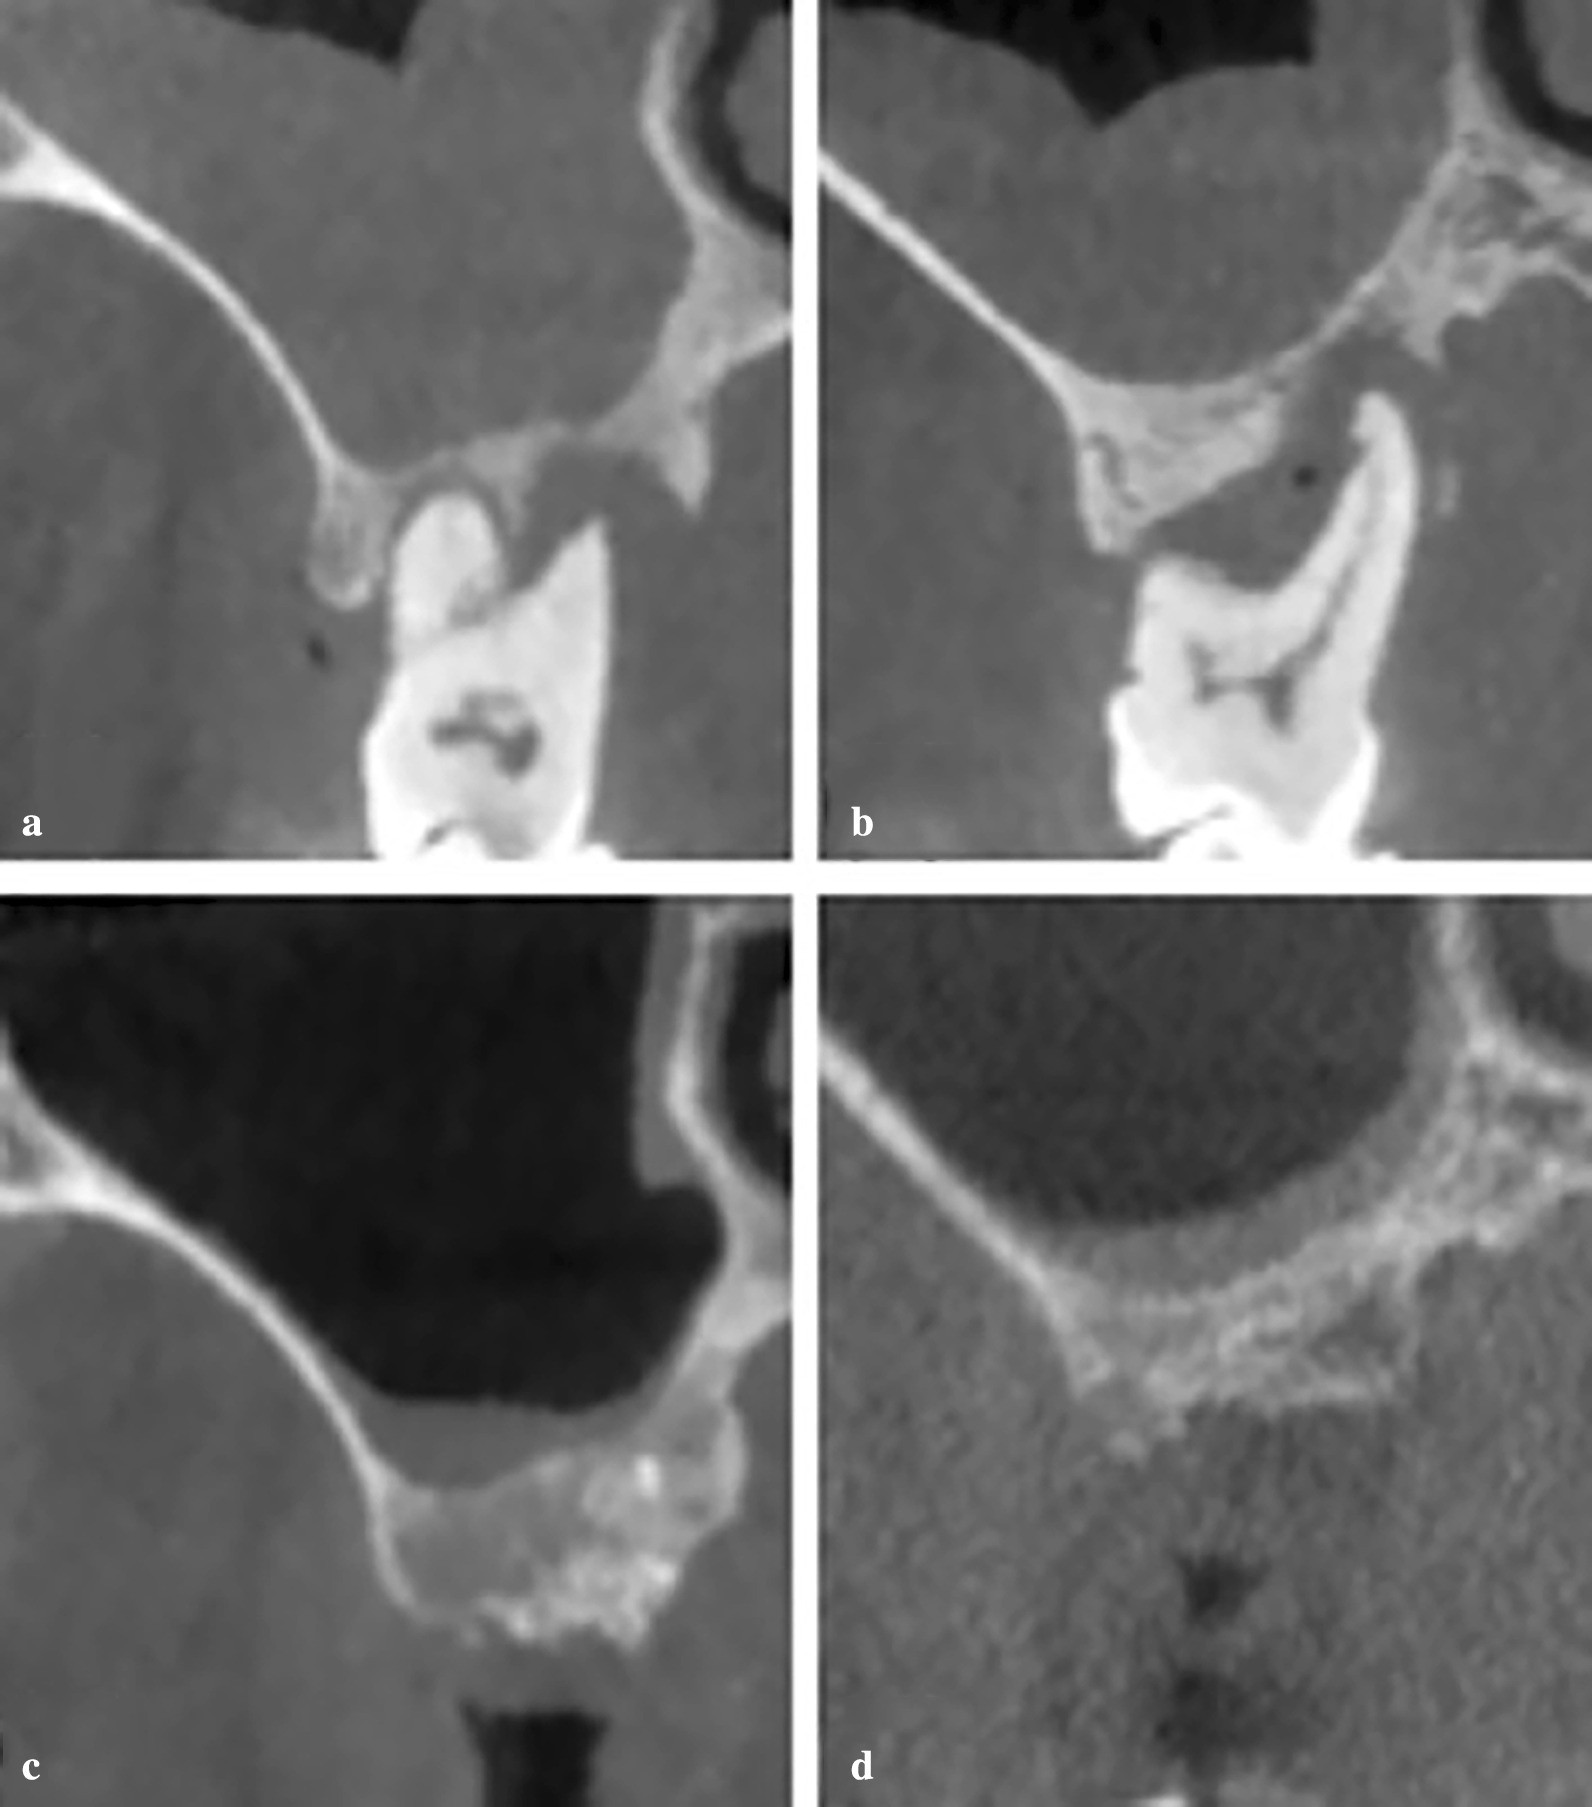

Fig. 3

Representative images of coronal-sectional CBCT scans from sinuses with thickened MT in the pre- and 6 months post-extraction of the test and control groups. a Pre-extraction maxillary sinus with thickened MT of the test group. b Pre-extraction maxillary sinus with thickened MT of the control group; c 6 months post-extraction of the test group; d 6 months post-extraction of the control group